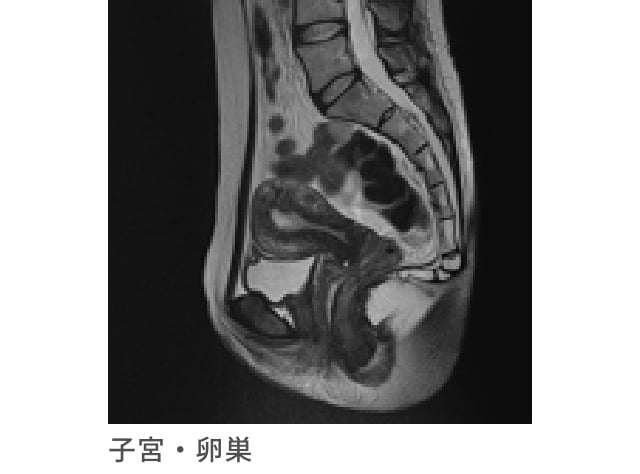

子宮・卵巣MRI検査

子宮や卵巣、婦人科疾患の診断に有効な検査です

超音波検査では得られない疾患、子宮筋腫や卵巣腫瘍の位置なども正確に得ることができます。

また、検査はベッドに横になって磁気を使って行う検査なので、X線被ばくもありません。

子宮頸がんの早期発見に有効な子宮頸部細胞診検査と合わせて実施することで、より精度の高い婦人科検査となります。